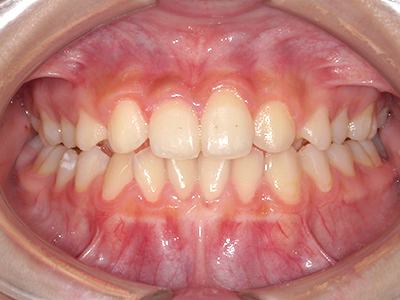

小児矯正について

ないき歯科クリニックでは、上あごの成長不足を補い、鼻呼吸を獲得しつつ歯列を整え、将来のお口をより健康な状態にすることをゴールに定める矯正治療をおこなっています。

矯正装置を装着し、調整しながら少しずつ歯を移動させ、歯並びを整えていきます。

状態によって家庭でのトレーニングが必要な場合もあり、治療期間も個人差があります。

あくまでも平均値ではありますが、一般的には月1回程度来院頂き、1~2年程度を目安に治療を進めていきます。